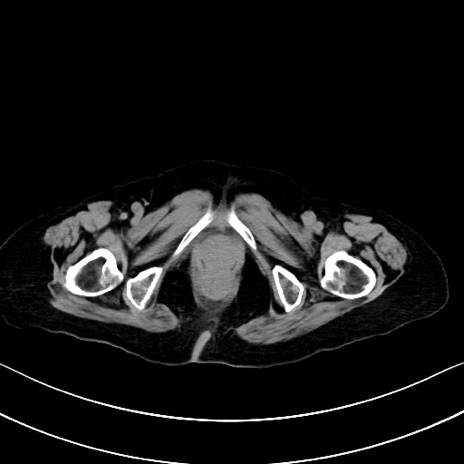

横断像

他院CT